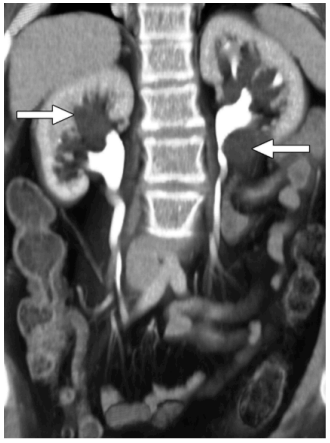

Paciente masculino, 52 anos, procurou o serviço de diagnóstico por imagem após encaminhamento

urológico devido a dor lombar discreta e episódica bilateral, associada a episódios de hipertensão arterial

de difícil controle nos últimos meses. Nega hematúria macroscópica, febre ou perda ponderal. Foi solicitado

exames de imagem para diagnóstico, onde foi obtida a seguinte imagem:

Figura 1: O’CONNOR, Owen J.; MAHER, Michael M. CT urography. American Journal of Roentgenology, v.

195, n. 5, p. W320–W324, nov. 2010. DOI: 10.2214/AJR.10.4198. Disponível em:

https://ajronline.org/doi/10.2214/AJR.10.4198

3.1) CITE o exame de imagem realizado e o plano anatômico da Figura 1.

• Exame: Tomografia computadorizada de abdome com contraste (TC abdominal com contraste).

• Plano anatômico: Corte coronal.

3.2) MENCIONE o contraste utilizado e a via de administração.

• Meio de contraste: Contraste iodado hidrossolúvel, preferencialmente não iônico e de baixo osmolar (ex.: ioexol, iopromida, ioversol).

• Via de administração: Endovenosa (IV) por bolus, geralmente através de acesso em veia antecubital.

3.3) INDIQUE os possíveis achados/suspeita diagnóstica demonstrados nas setas da Figura 1.

As imagens sugerem presença de lesões renais ocupantes de espaço bilaterais — a hipótese mais provável é neoplasia (RCC multifocal ou metástases). Diferenciação exige TC abdominal com fases pós-contraste ou RM com gadolínio, além de correlação clínica, exames laboratoriais e possível biópsia percutânea conforme necessidade.